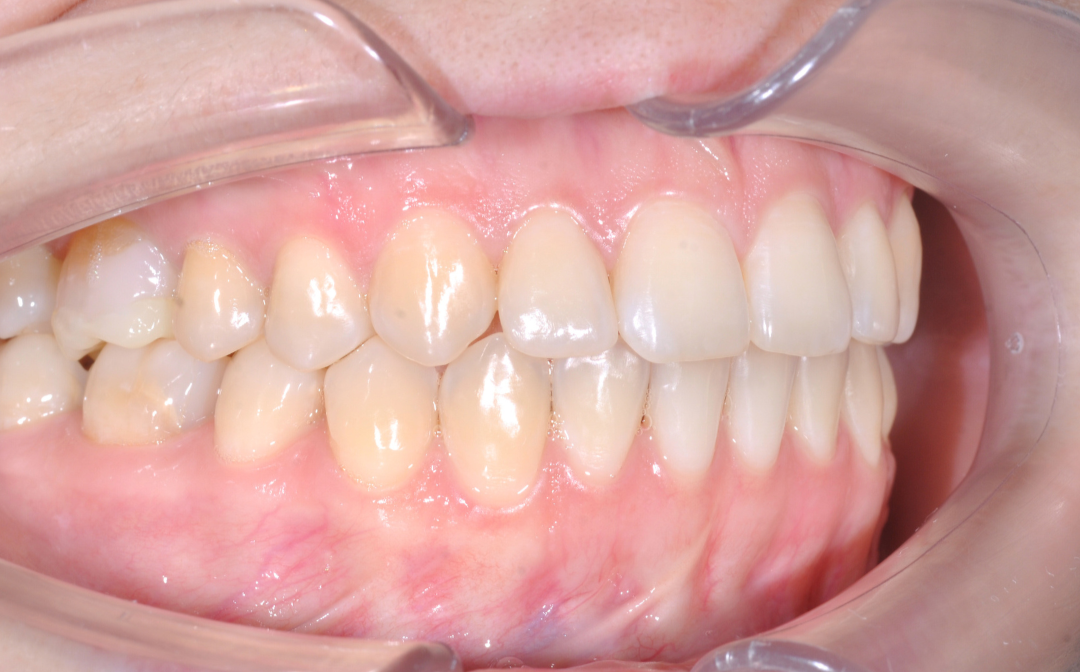

Этап №3

Ортодонтическая коррекция.

Стоматолог-ортодонт зафиксировал комбинированную брекет-систему (сверху керамические, а снизу – металлические брекеты).

Ключевые задачи ортодонта:

- Исправление прямого прикуса (одной из частых причин дисфункции ВНЧС).

- Изменение положения зубов.

- Доведение контактов челюстей до физиологически правильного смыкания.